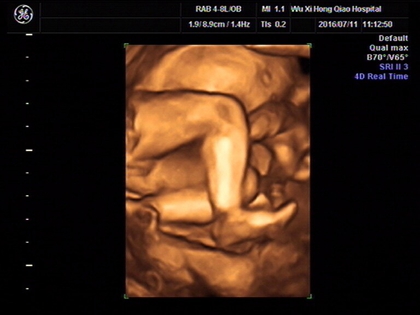

四维胎儿手呈握拳状一般都是男孩吗?

这个说法也是没有科学依据的,宝宝在妈妈的体内会胎动,并且四肢都是可以活动的,宝宝在子宫内手握拳是非常正常的现象,不管是男女宝宝都是这样的,并不能来判断男女。

许多婴儿在妈妈的子宫腔中都是有四肢、手脚有变小的变动,是正常情况,胎儿双手呈握拳状也是正常的。如果有特殊情况,医生一般都会及时通知,也有很大可能是宝宝是检查时处于睡眠状态。也可以根据检测出的各个数据来判断胎儿的发育情况。

男孩一般胎儿四维手呈握拳状